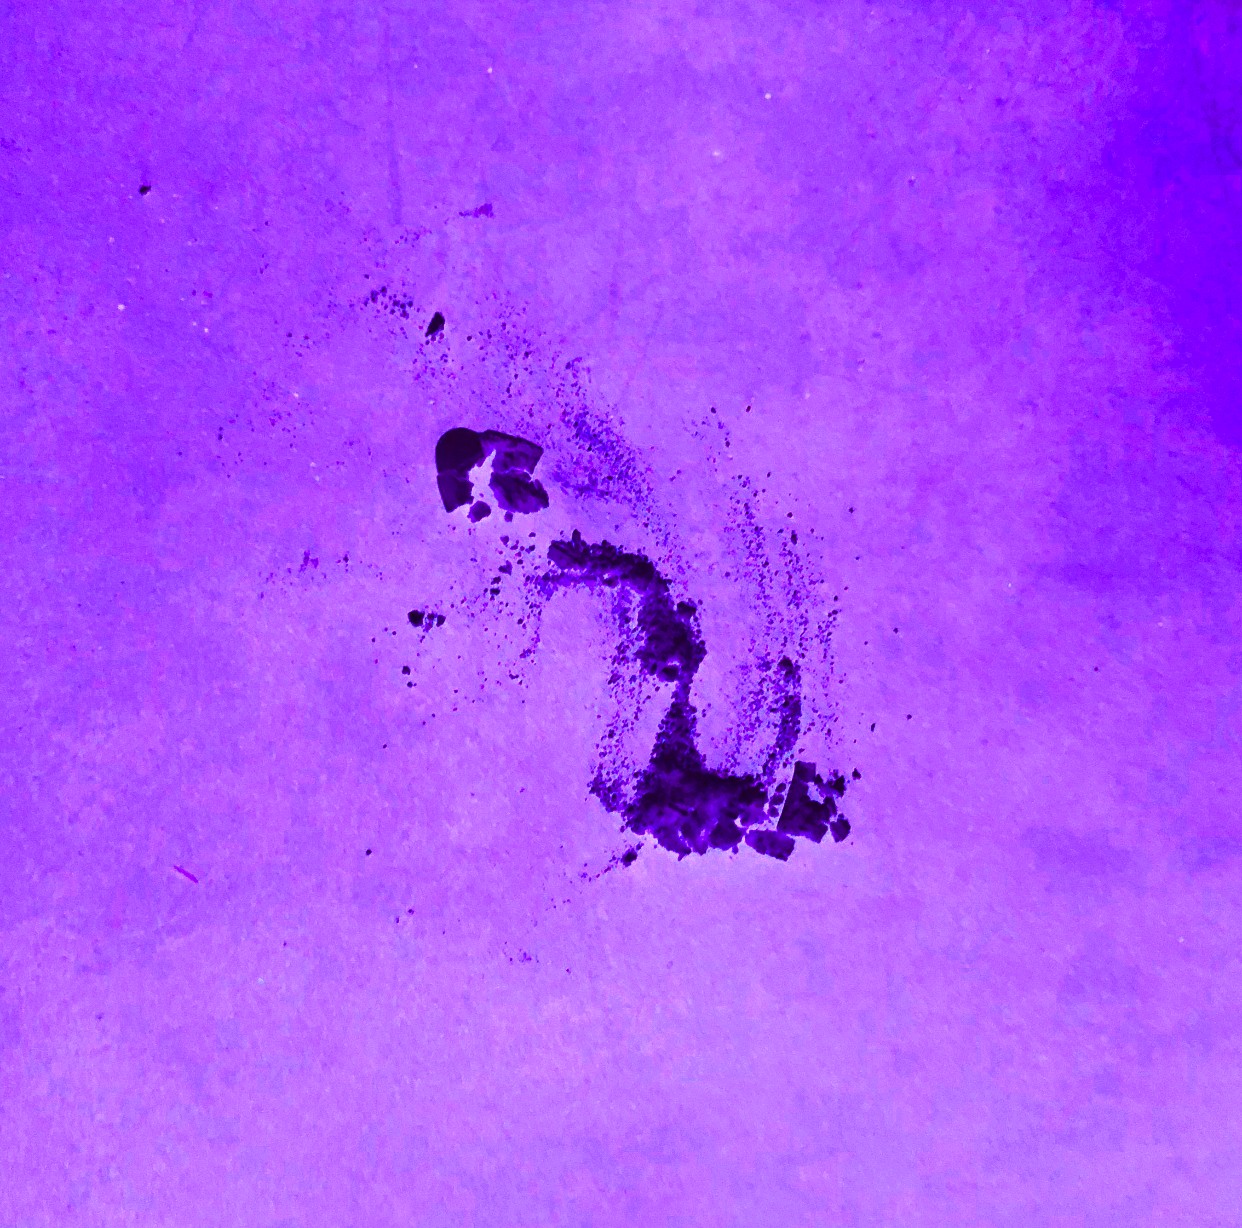

In my frustration I dumped a bunch of those pills out they were pretty, I snapped a pic. The meds I was to discontinue got their farewell by being crushed, I took a pic. I liked it, it made me feel like something other than a patient. I spelled out symptoms with their corresponding pills, sometimes taking hours more pictures.

I had wanted to be one of those cool artists that did photo diaries or Vlogs of the whole illness. I was far too out of it, between the pain and the meds, to even think about doing something like that. With help, I began digitally manipulating them to make them more colorful and textural, it gave me hope amidst the mess.

I was hurting and it helped. Aren’t we all hurting? Each person has their own mess to deal with. Many stop to take a picture of something that causes a stir in them. I want to share what gave me hope through the web of treatments, trauma, and a myriad of medication.